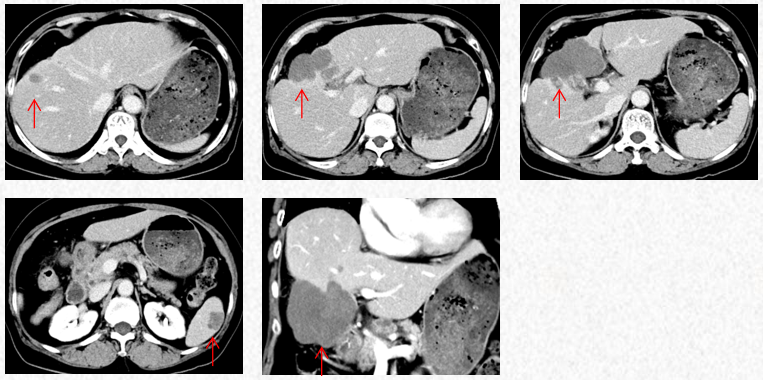

2023-7-15复查胸腹CT图片,疗效评估为SD,轻度双上肢麻木,生活不受影响。

2023-7-15胸腹CT:肝肿物最大横截面积86*58mm,脾脏转移瘤(19*12mm)